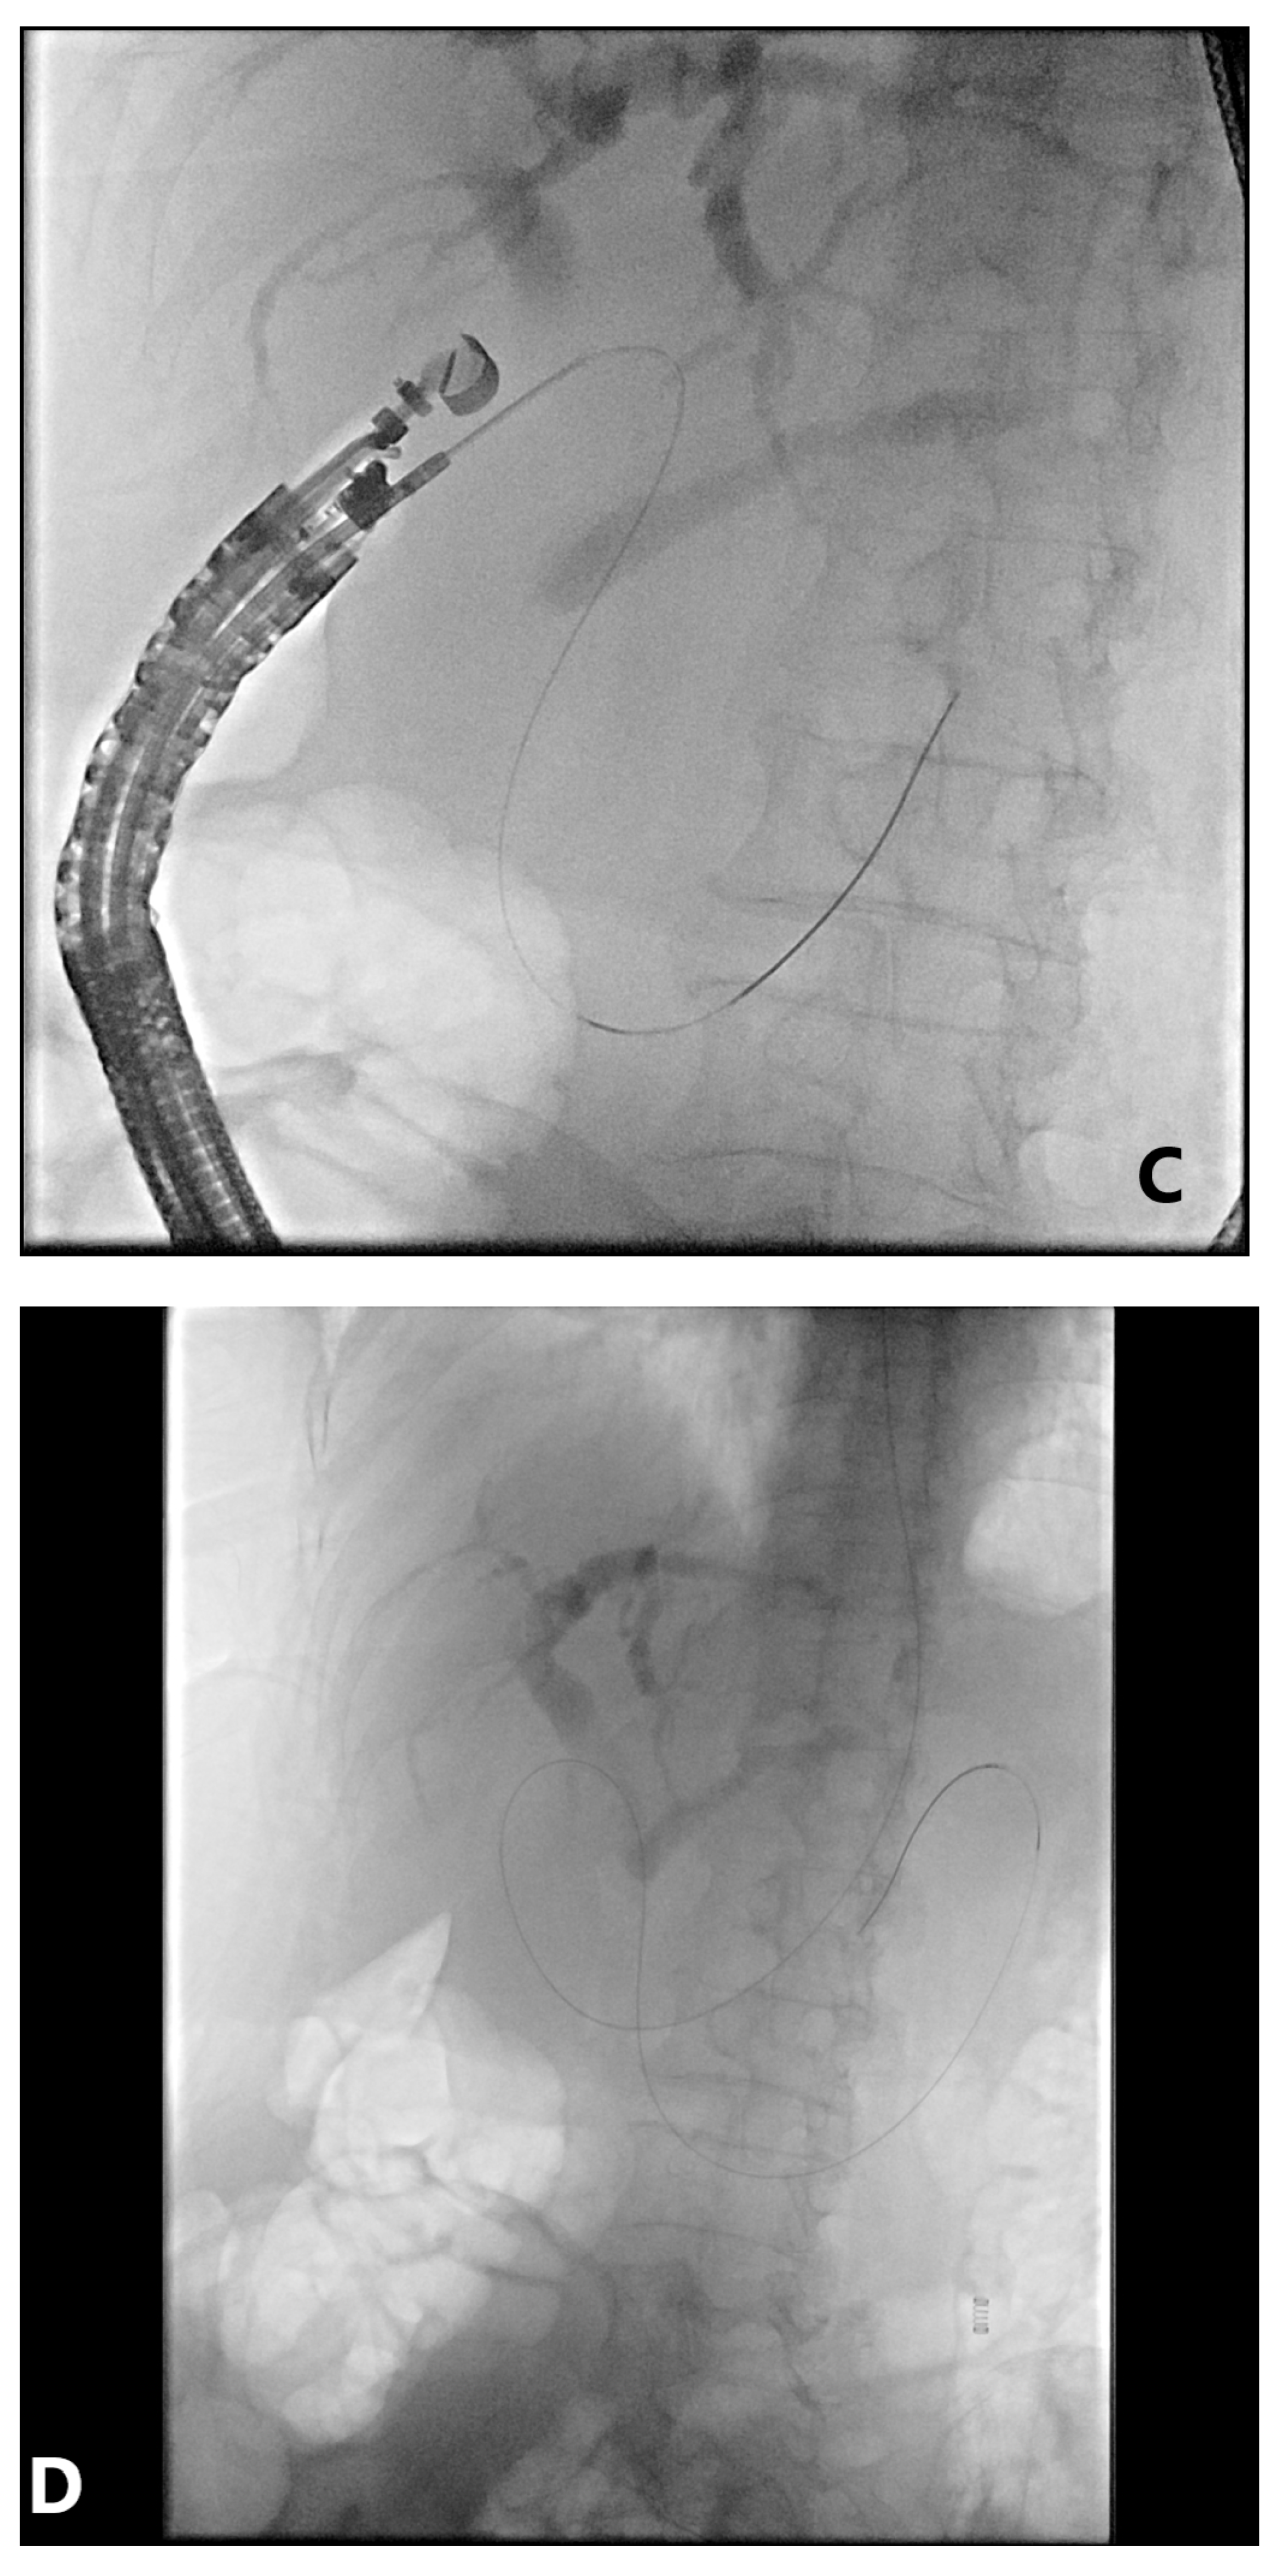

4. EUS-Guided Rendezvous (EUS-RV) Technique